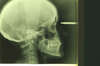

Les radios avant le traitement